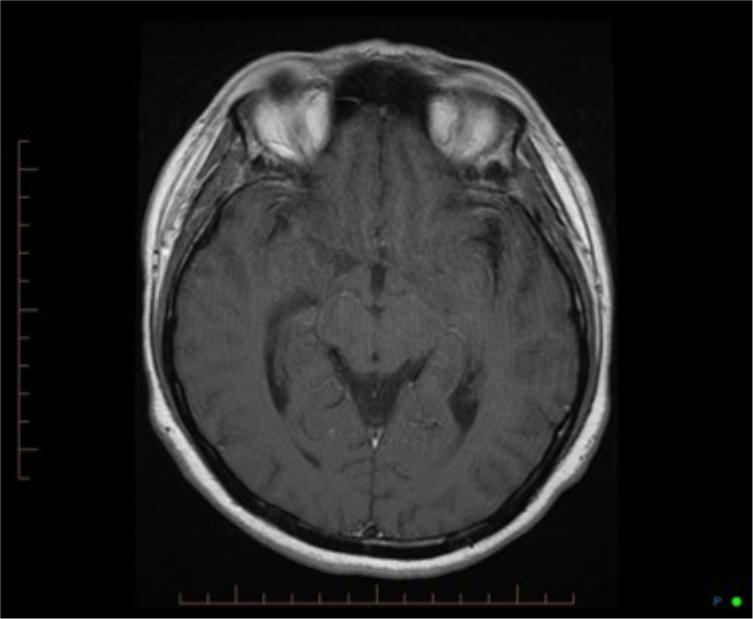

Pictured above is the patient’s admission MRI, which also showed subtle changes indicative of TB Meningitis.

Milary TB is a form TB where bacteria first enters the host by droplet inhalation (Ramachandran, 2014). This, at first a localised infection, usually starts within the lungs causing tiny tubercles that appear like “millet seeds” in size and appearance, hence the name “miliary” (Sharma, Mohan & Sharma, 2012). These seed-like infective sites can spread to other regions through the blood-stream that eventually reach the brain causing small abscesses that burst in the subarachnoid space resulting in TB Meningitis (TBM) (Ramachandran, 2014). The abscesses appear on MRI’s as small lesions (Cherian & Thomas, 2011), such as in the scan on the previous slide.